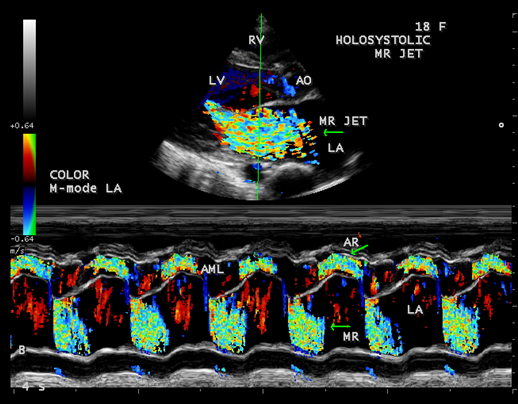

Figure 14. Color-flow M-mode showing the holosystolic mitral regurgitation jet in a 18-year old girl

The extreme dilatation of the left atrium is probably related to the jet of regurgitation (or insufficiency), a finding common to all as shown in Figure 12, the jet occupies the entire left atrium as in Figure 13 and a holosystolic pattern in color M-mode echocardiography as shown in Figure 14.